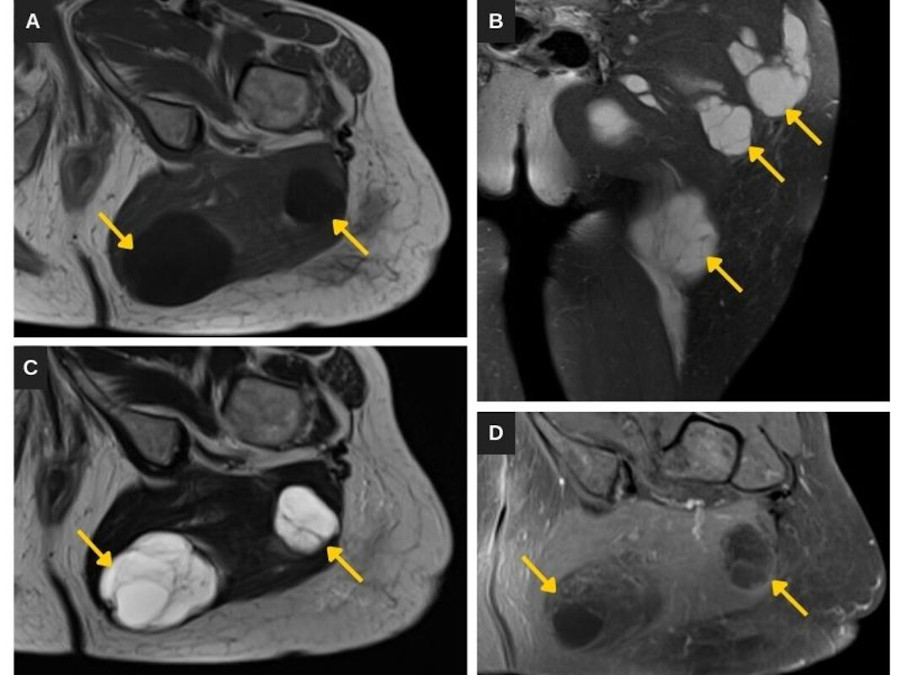

La RM muestra múltiples masas intramusculares en el brazo derecho (Fig. 1) y la región glútea izquierda (Fig. 2), de contornos netos, señal baja potenciada en T1 y alta en T2/STIR, y captación heterogénea del gadolinio.

Las masas intramusculares muestran las características típicas de mixomas por RM, que consisten en márgenes bien definidos, señal relativamente homogénea, baja en T1 y alta en T2/DP, y captación de contraste predominantemente periférica y central heterogénea. El realce periférico se debe a la presencia de abundantes vasos sanguíneos en la pseudocápsula, mientras que la captación central heterogénea se debe a septos fibrosos y tejido mixoide sólido10. Estas características, sumadas a la presentación clínica, su multiplicidad y la localización típica adyacente a la displasia fibrosa, permiten diferenciar los mixomas de otras lesiones quísticas de naturaleza más homogénea y de algunos sarcomas de partes blandas.